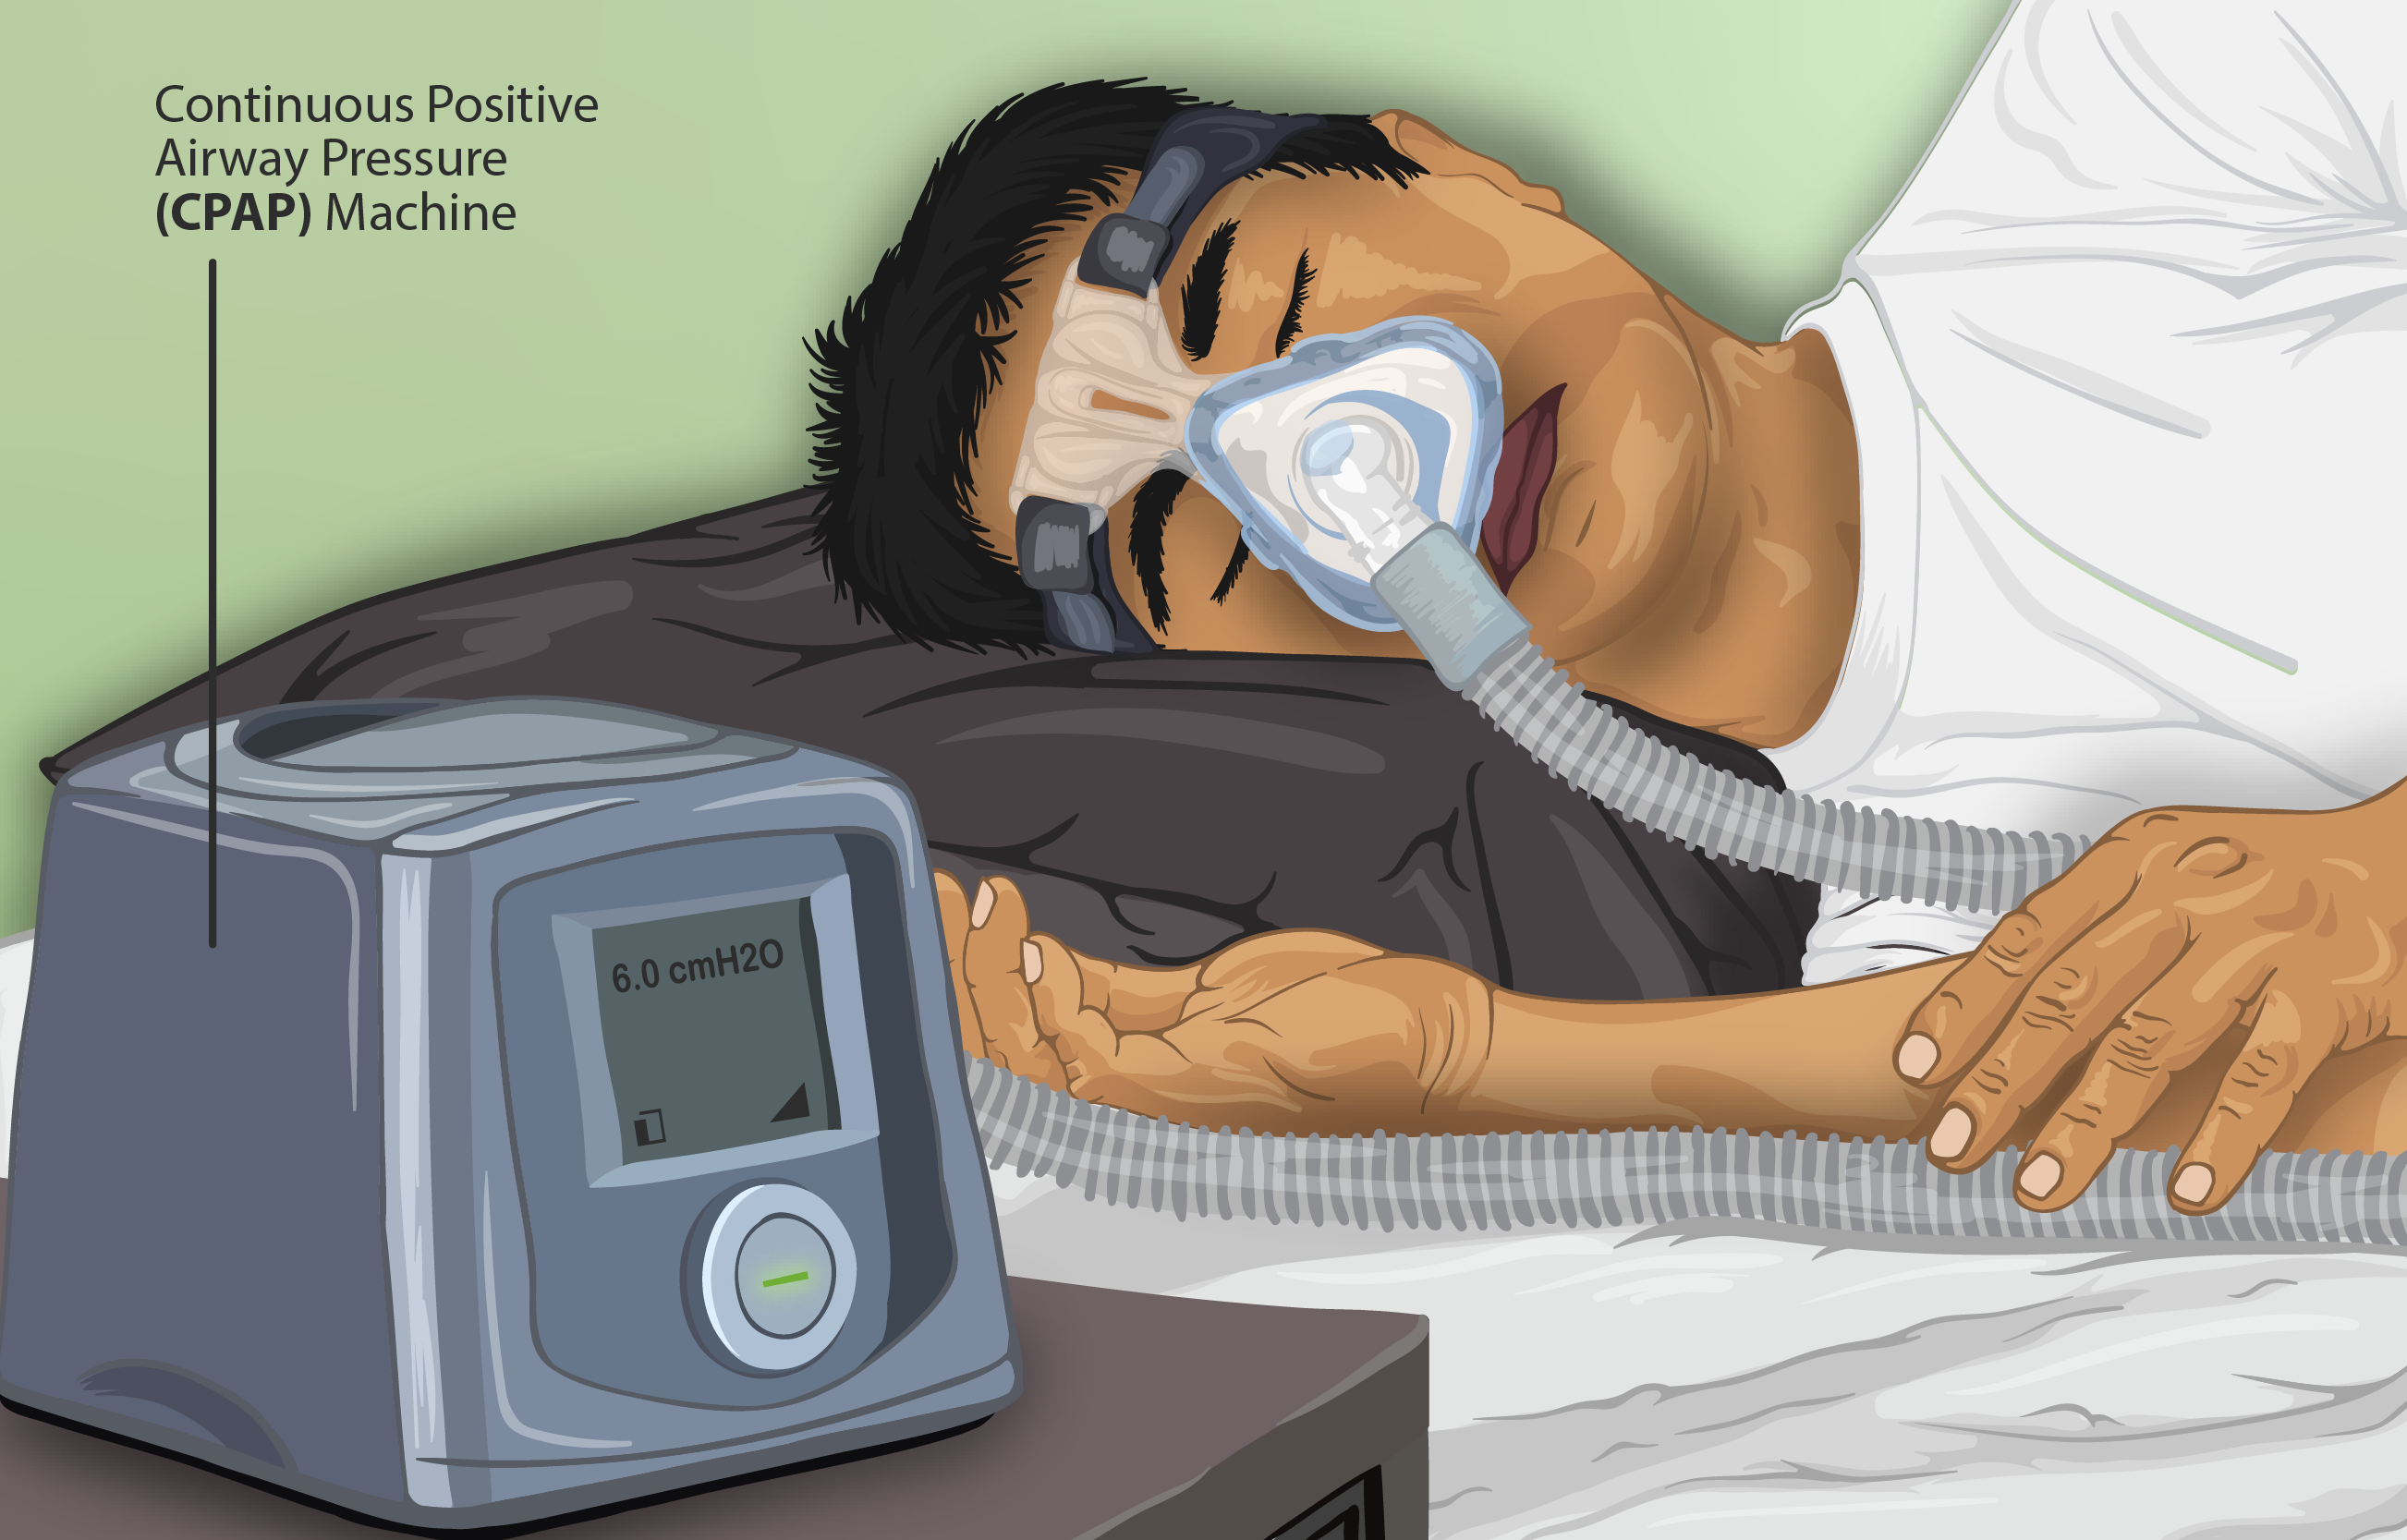

- Continuous positive airway pressure (CPAP) – machine supplied continuous positive pressure during the entire breathing cycle causing better oxygenation by narrowing the shunt (i.e., inadequate alveolar ventilation). This is generally using in high dependency units.